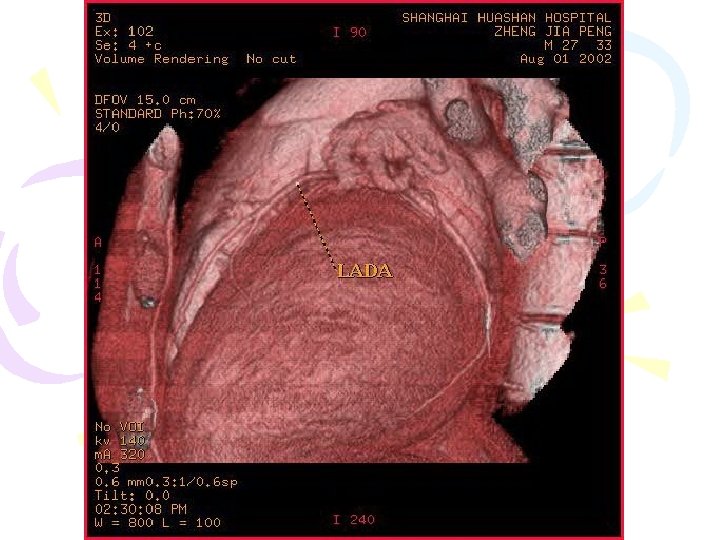

CT Axial & 3 D Image